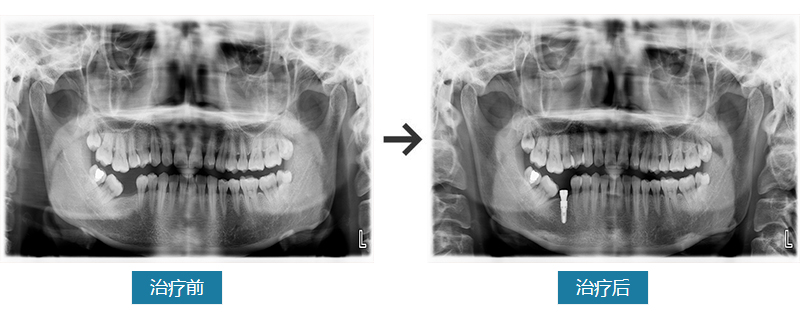

口腔卫生一般,牙龈粉红,质韧,牙颈部少量软垢,牙结石(-)。咬合关系未见异常。46缺失。X线显示缺牙区骨小梁清晰,骨质密度III类。

种植修复。必兰局部浸润麻醉46,进行种植。十天后拆线,3-6个月行种植冠修复。

张女士四十来岁,右后牙缺失。张女士说之前是虫牙,后来牙洞越来越大,最后就掉没了。少了一颗牙后,感觉右边咬东西没有那么方便了,只好用左侧牙齿咀嚼。但是看健康类文章说是单侧咀嚼不好,就来到西安拜尔口腔问诊,由种植专家倪医生接诊。根据片子和检查结果,张女士符合种植牙的条件和标准。倪医生结合检查结果和张女士的诉求,给出详细的治疗方案和计划。张女士说自己开始有点害怕,但是看过我们的病例展示、并和倪医生交谈后,医院、医生的专业素质和认真态度让她打消了疑虑,决定种植。

5个月后,张女士结束了所有的种植环节,戴牙成功。她说非常好,舒适自然,跟旁边的真牙一样好使。虽是假牙,但也不用每天卸下来清理,非常适合懒人。